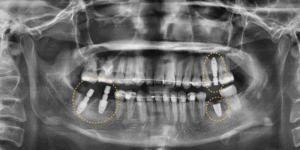

임플란트 보철까지 완성한 모습입니다.

치아교정 종료 후 고정성 유지장치를 통해

이후 교정이 마무리 단계에 접어들 무렵

결손된 어금니 부위에 임플란트를 식립하여

교정 종료 시점과 임플란트의

보철 완성 시점을 일치시킬 수 있었습니다.

교정으로 만들어진 이상적인 교합 관계 위에

임플란트가 안정적으로 자리 잡았습니다.